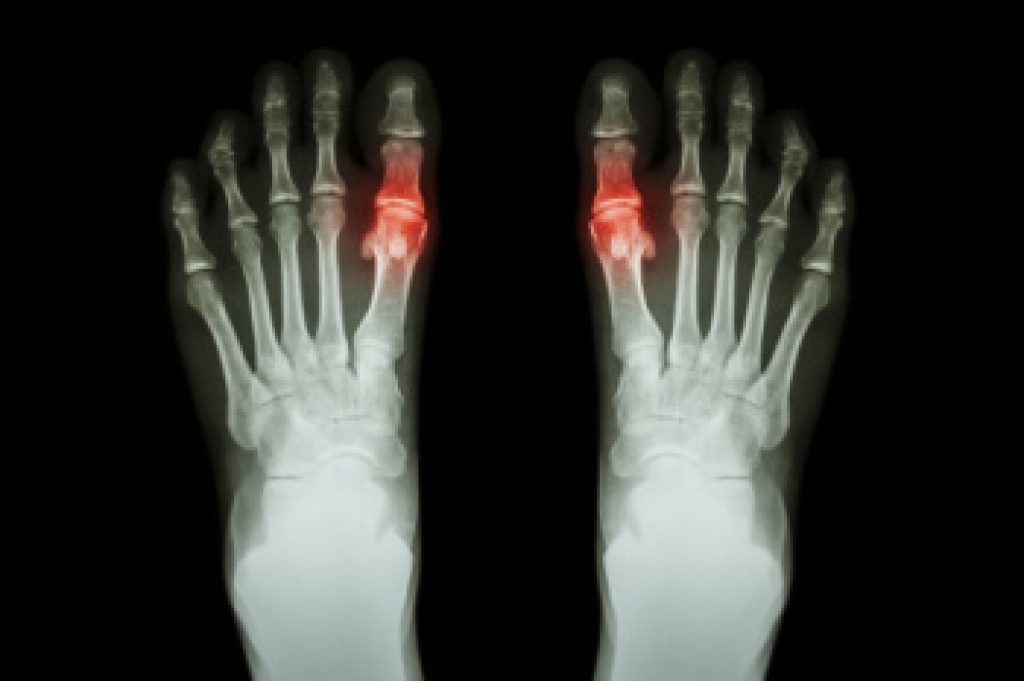

Foot and ankle injuries are a common occurrence when it comes to athletes of any sport. While many athletes dismiss the initial aches and pains, the truth is that ignoring potential foot and ankle injuries can lead to serious problems. As athletes continue to place pressure and strain the area further, a mild injury can turn into something as serious as a rupture and may lead to a permanent disability. There are many factors that contribute to sports related foot and ankle injuries, which include failure to warm up properly, not providing support or wearing bad footwear. Common injuries and conditions athletes face, including:

Sports related injuries are commonly treated using the RICE method. This includes rest, applying ice to the injured area, compression and elevating the ankle. More serious sprains and injuries may require surgery, which could include arthroscopic and reconstructive surgery. Rehabilitation and therapy may also be required in order to get any recovering athlete to become fully functional again. Any unusual aches and pains an athlete sustains must be evaluated by a licensed, reputable medical professional.